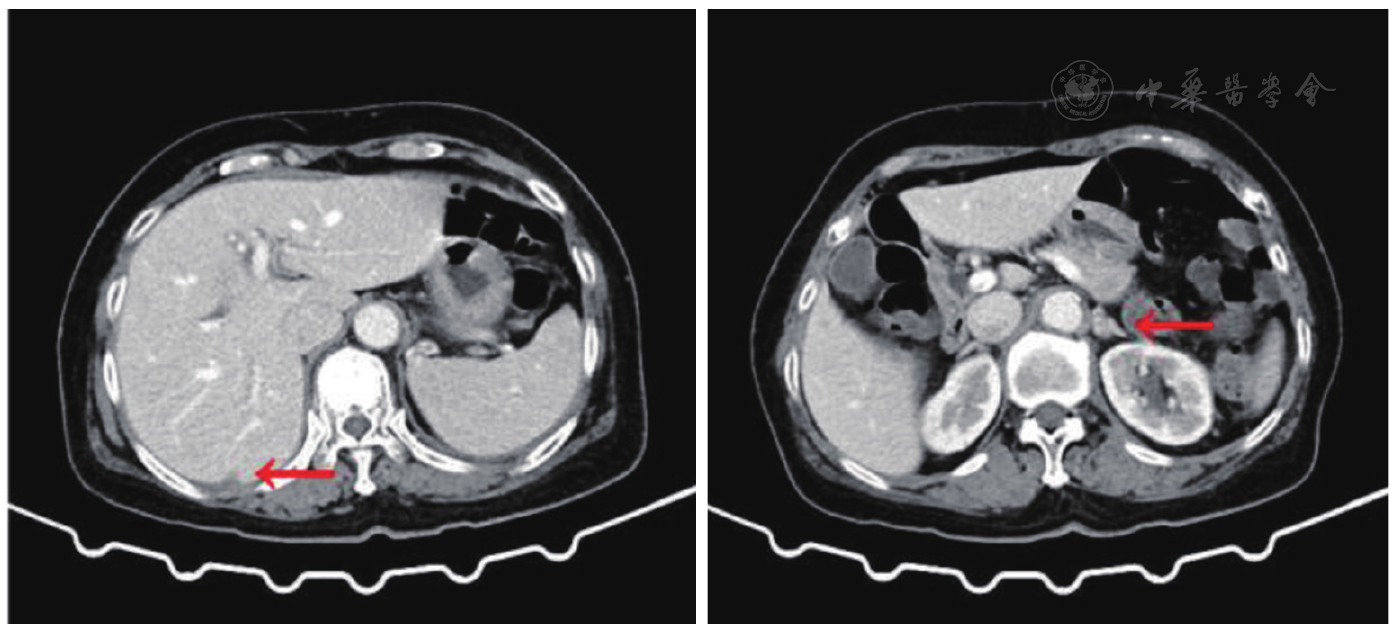

图3 肺腺泡细胞癌病理染色图片(HE,×200)。HE:苏木精-伊红染色